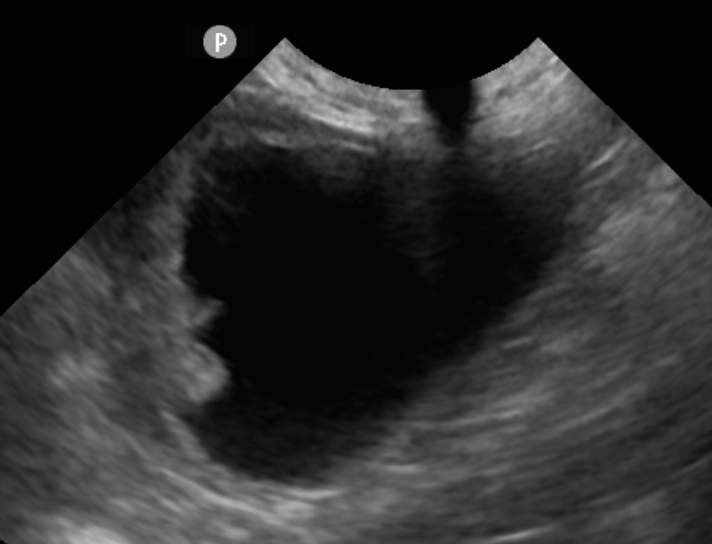

因此,本院選擇用無創內視鏡,直接從尿道進入膀胱採樣,術後當天可以直接回家,不用傷口照護

團塊位於膀胱APEX所以可以較大範圍切除,術後持續治療,到現在一年半,目前沒有復發或是轉移跡象

大部分狗狗的膀胱上皮細胞癌都長在三角區的部位無法評估手術切除,所以妞妞是很幸運的毛小孩喔